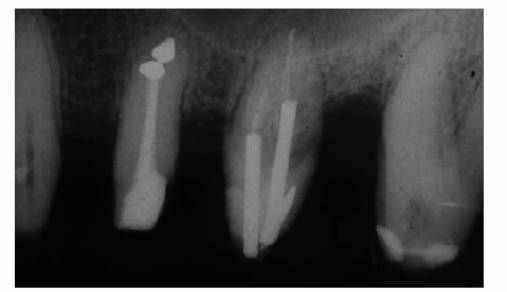

Figure 19-37A: View of maxillary central incisors following excavation of extensive caries. The pulps were not exposed.

Figure 19-37B: Radiograph of the same teeth. Note the minimal thickness of dentin adjacent to the pulp chambers.

Figure 19-37C: Root canal therapy completed on the maxillary central incisors.

that the pulps would not survive another restorative procedure (Figures 19-37A 19-37B, and 19-37C). According to Abou-Rass's

criteria, further insult to the affected (stressed) pulpal tissue would

probably invite disaster. An intelligent decision would be elective

endodontics, thereby intercepting potential problems.